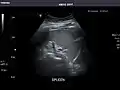

- Spleen

Spleen: Normal in size.